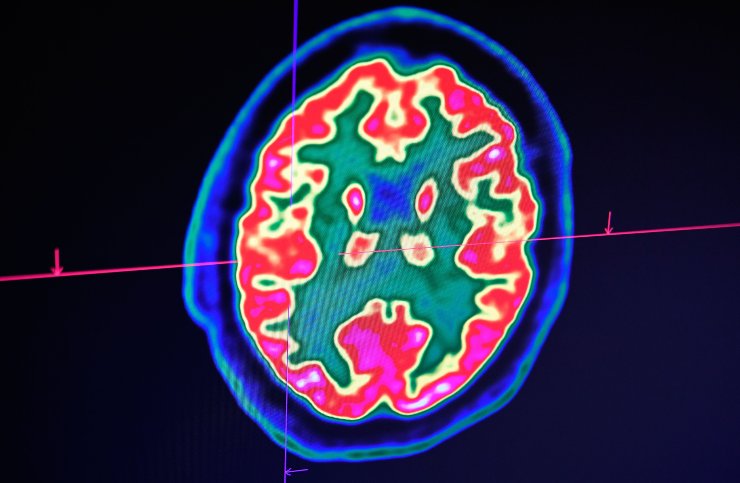

L’eccesso di potere, certo, ma anche l’insicurezza provoca decisamente brutti scherzi. Questa situazione si acuisce nella prima fase del sonno; il cervello, a riposo, fa una sorta di backup della giornata, analizzando i dati e le situazioni vissute durante il giorno trascorso.

Ed è in questa fase che, se la nostra mente evidenzia stati di insicurezza o ansia, le trasmette all’intero corpo durante il primo sonno, inglobando nelle reazioni anche i sistemi muscolare e nervoso.